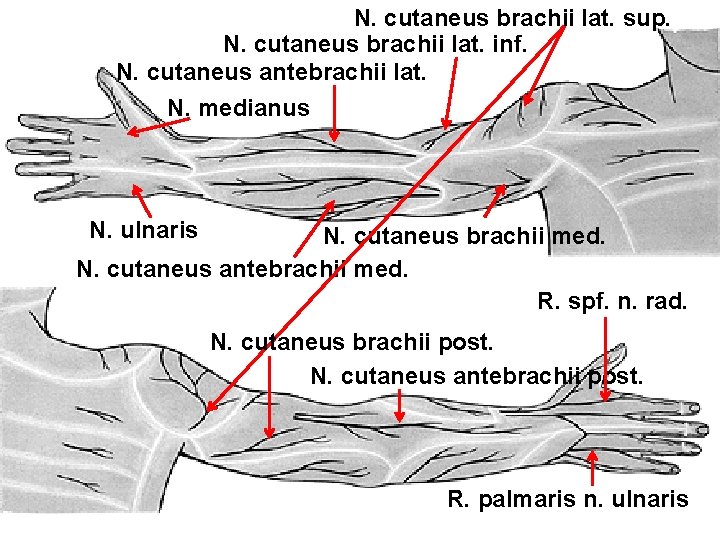

N. cutaneus brachii lat. sup. N. cutaneus brachii lat. inf. N. cutaneus antebrachii lat. N. medianus N. ulnaris N. cutaneus brachii med. N. cutaneus antebrachii med. R. spf. n. rad. N. cutaneus brachii post. N. cutaneus antebrachii post. R. palmaris n. ulnaris